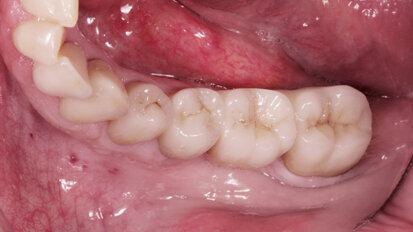

Rehabilitace Straumann